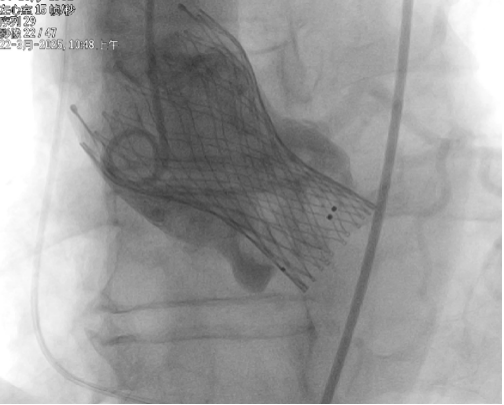

VenusAL26瓣膜释放至2/3

超声查看无瓣周漏

术后经导管测压显示,跨瓣压差由术前的62mmHg降低为8.75mmHg,血流动力学极大改善,超声提示人工瓣膜工作状态良好、微量瓣周漏。